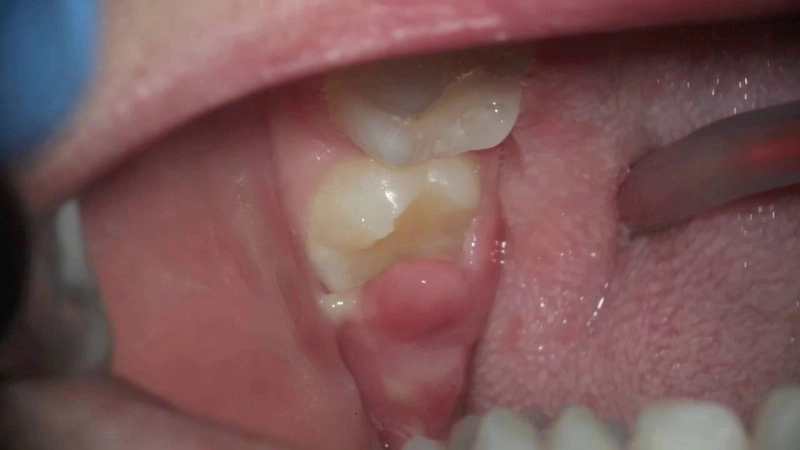

Viêm lợi trùm là thuật ngữ nha khoa mô tả tình trạng mô nướu mềm xung quanh chiếc răng đang mọc bị sưng viêm và nhiễm trùng (đặc biệt là vị trí của răng số 8). Khi răng khôn không thể mọc lên hoàn toàn do thiếu không gian hoặc mọc lệch, một phần nướu phía trên sẽ bao phủ lấy bề mặt răng, tạo thành vạt nướu. Từ đó thức ăn, mảng bám và vi khuẩn dễ dàng tích tụ, dẫn đến hiện tượng viêm nhiễm, gây đau nhức và sưng tấy.

Sưng phồng: Mô lợi trùm bị viêm, căng lên, đôi khi bao phủ gần hết mặt nhai của răng khôn.

Vì vậy, việc phát hiện sớm, nhìn nhận đúng mức độ nghiêm trọng qua các dấu hiệu, hình ảnh viêm lợi trùm và điều trị dứt điểm tại cơ sở nha khoa uy tín là vô cùng cần thiết.